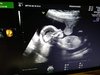

Dziewczyny ja już po wizycie wszystko w porządku no i będzie chłopak [emoji173] bardzo urósł od ostatniej wizyty termin z om 3.04, z poprzedniego usg wychodziło 1.04 z dziś 25.03 [emoji39] waga 210g z tego co pamiętam

U nas wszystko w jak najlepszym porządku, dzidzia podskakiwala wkladala sobie rączki do buzi i ciągle machala nóżkami. Ma już 20 cm, serduszko pięknie biło, polowkowe mam 23.11 chociaż moja dr już dzisiaj powiedziała że nie musiała by robić za miesiąc bo już teraz widać że wszystko jest w jak największym porządku :)

A oto nasza księżniczka [emoji7]